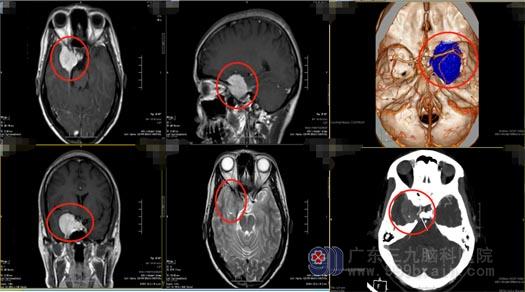

随后的时间里,柯女士出现肢体抽搐十几次,伴随着右眼视力逐渐下降,在当地医院检查,头颅MR提示:右侧鞍旁稍高密度占位性病变内血管丰富,考虑脑膜瘤,病变包绕右侧颈内动脉虹吸段,右侧大脑中动脉受推挤向内上方偏移。入住广东三九脑科医院神经外五科后,进一步检查发现患者的右侧眼球无法充分向上、向外活动,肿瘤已经侵袭大血管及海绵窦,病变血供丰富且包绕颈内动脉。

蝶骨嵴脑膜瘤由于位置比较特殊,肿瘤和血管神经粘连紧密,不仅病变切除难度大,同时手术出血风险也极大。需要完善全面的术前评估进行保障,极为专业的手术团队进行配合,有相当丰富手术经验的医生才可进行手术。如果没有做到全切除,肿瘤易复发,可能需要再次手术;术中若损伤瘤体周围神经血管,则可能导致患者残疾,甚至危及生命。随着肿瘤的生长,蝶骨嵴脑膜瘤会逐渐压迫神经和动脉,手术难度也会进一步提高。

医院副院长、神经外五科主任鲁明带领治疗团队为柯女士先进行了脑血管造影+Allen试验+Bot试验,预先了解肿瘤及颅内血供情况,排除了手术禁忌症,为患者实施了“右侧鞍旁-蝶骨嵴脑膜瘤切除术+右侧颞浅动脉-右侧大脑中动脉血管搭桥术”,术中发现颈内动脉被肿瘤严重侵犯,对颈内动脉进行了破口夹闭。手术顺利。柯女士术后恢复得很好,四肢活动正常,很快就办理了出院,一家人都非常满意手术效果。术后病理结果提示:过渡型脑膜瘤(WHO1级)。复查头颅MR提示原病灶已切除。